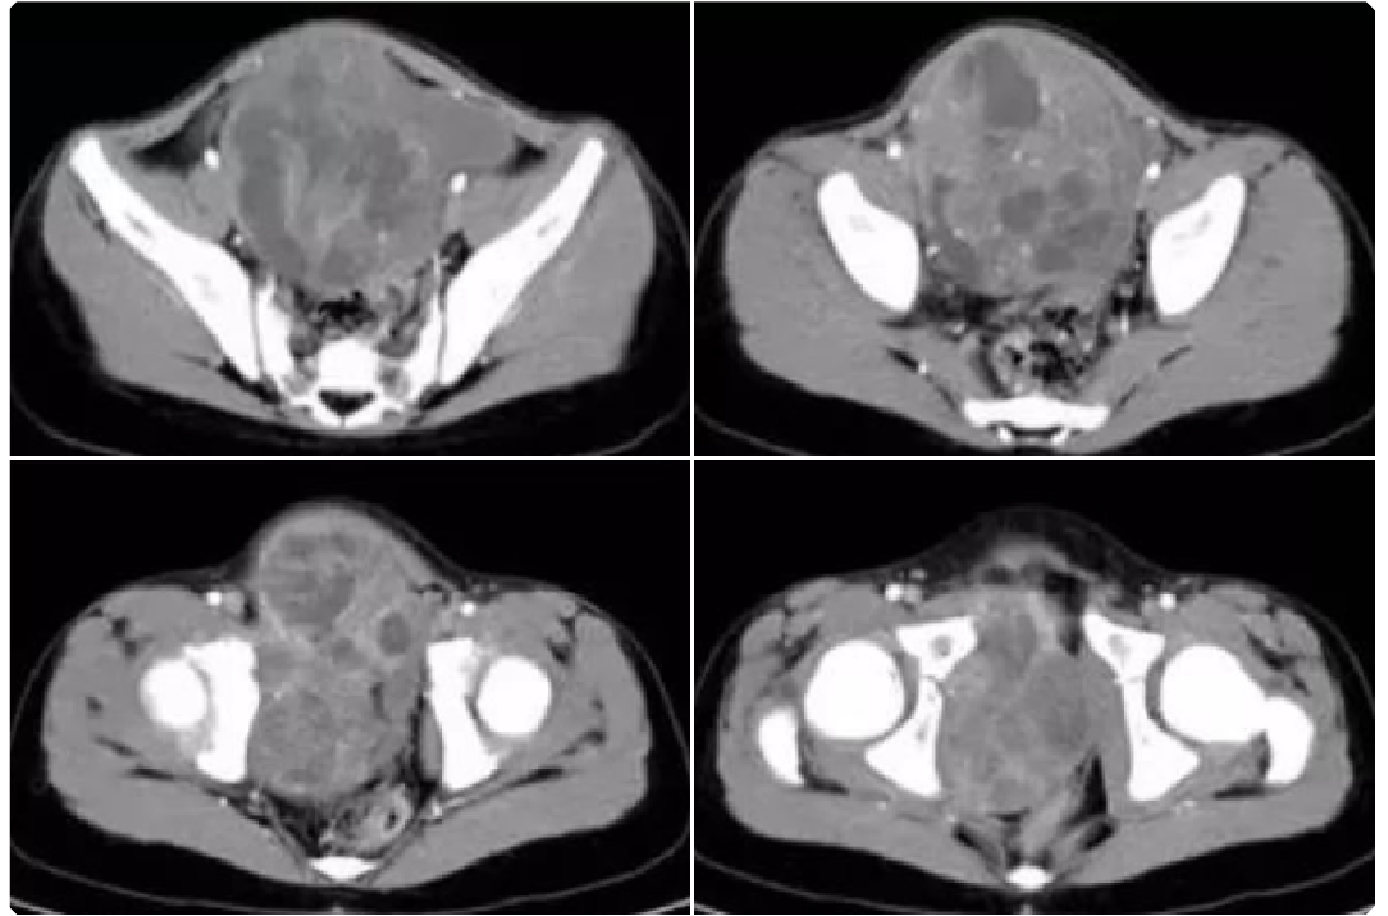

47df5e91be9763c0283a82cb0256446c.png 病例 23:(盆腔内)神经鞘瘤  46岁女性,因发现腹部肿块10余年,腹部隐痛1月余,实验室检查无特殊a1-a4为横断位多个层面;b1-b2为冠状位两个层面;c1-c2为矢状位两个层面;d为动脉和肿瘤的三维成像。肿瘤可见包膜,瘤体可见明显囊变坏死。免疫组化:S-100(+)、SOX-10(+)、CD117(-)、Dog-1(-)、 SMA(-)、Ki-67 (+,<1%)。特殊染色:PAS、网染无特殊。